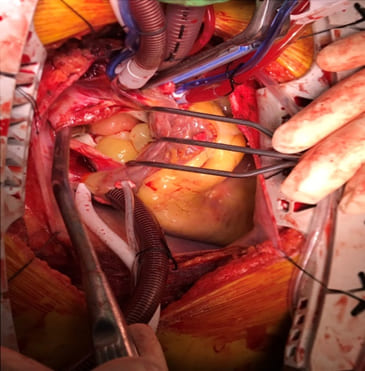

A 26-year-old female with no known medical history presented to our hospital for consultation regarding a cardiac mass found during a transthoracic echocardiogram. The patient complained of fever, bloody sputum for several days, progressive exertional dyspnea, and paroxysmal nocturnal dyspnea for a few months. The results of the laboratory tests were insignificant. Chest CT revealed a large isoechoic mass in the left atrium (Figure 1), as well as shown in transthoracic echocardiography with tricuspid regurgitation, pulmonary hypertension, and right heart systolic dysfunction. Under cardiopulmonary bypass and the guidance of transesophageal echocardiography, tumor excision, mitral annuloplasty, and tricuspid annuloplasty were performed (Figure 2). Histological examination revealed predominantly a hypocellular myxoid tumor, composed of spindle-to-round cells within a myxoid matrix (Figure 3). We observed a focal area of increased cellularity with mild to moderate nuclear pleomorphism. Mitotic activity was rarely identified. A focal myxoid degeneration and infarct-type necrosis were observed. The tumor was reminiscent of cardiac myxoma due to its predominantly myxoid matrix.

Figure 2: Intraoperative image: The large left atrium tumor and multiple round tumors adhesion to left atrium intraoperatively.